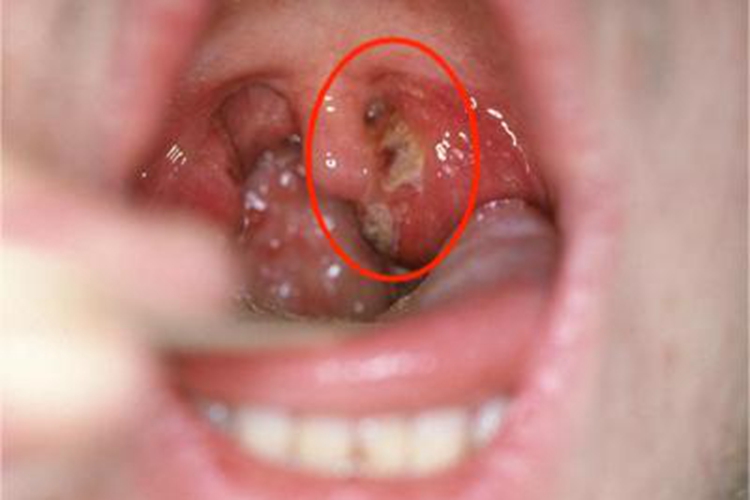

急性咽炎起病较急,先有咽部干燥、灼热,继有明显咽痛,吞咽时尤重,有时可伴有发热、头痛、食欲减退和四肢酸痛等。检查可见口咽部黏膜呈急性弥漫性充血、肿胀,表面可见黄白色点状渗出物,可伴随悬雍垂水肿。